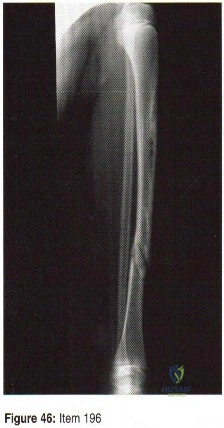

- A patient has a grade 2 open tibial fracture with 70% cross sectional bone loss that extends 2 cm in length. Treatment consists of stabilization with a nonreamed interlocking nail and successful secondary wound closure. Four months after the injury, no callus is visible. Management at this time should include which of the following?